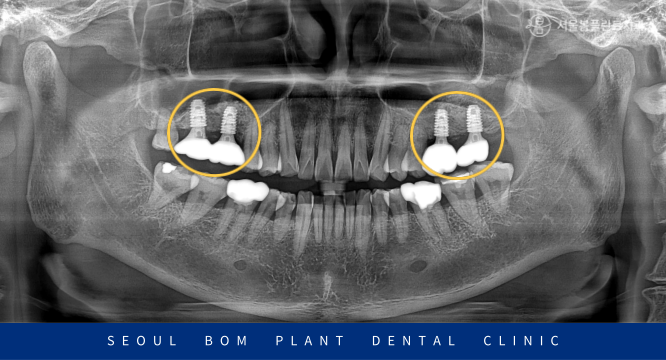

술 후 파노라마와 3D-CT 촬영을 통해

상악동 거상술을 동반한 임플란트가

안정적으로 식립된 것을 확인하였답니다.

임플란트와 잇몸뼈가 단단히

결합될 때까지 충분히 기다린 뒤

보철 과정까지 성공적으로

마무리해 드렸습니다.

환자분께서는 임플란트 식립을 통해

양측 저작을 편하게 할 수 있게 되어서

만족감이 높다고 얘기해 주셨습니다.